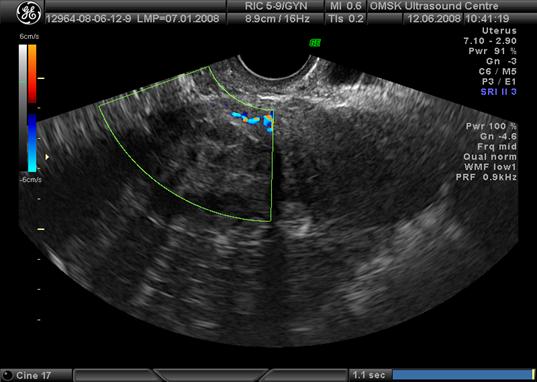

У 96 женщины основной и контрольной групп в доминантных миоматозных узлах проводилось исследование кровотока. При допплерометрии обнаружено два типа кровотока в миоматозных узлах у 69 пациенток основной группы: у 31,7% пациенток - нодулярный и у 68,3% - перинодулярный тип кровотока (рис.2, 3). В контрольной группе (27 пациенток) – точечный тип кровотока, независимо от размеров доминантных узлов. Для дальнейшего определения возможных патогенетических механизмов роста лейомиомы матки исследован индекс резистентности (ИР) в кровотоке доминантных узлов. Оказалось, что при лейомиомах с быстрым ростом узлов малых размеров по сравнению идентичными размерами узлов лейомиомы матки с медленным ростом узлов имеет место значительное превышение ИР - в 1,8 раза. Показатели ИР в доминантных узлах женщин основной группы нами были расценены как «пролиферативный» тип кровотока, определение которого, по нашему мнению, определяет подход к ведению пациентки независимо от размеров лейомиомы матки.

Рис.3 Перинодулярный тип кровотока по данным УЗИ с допплерометрией